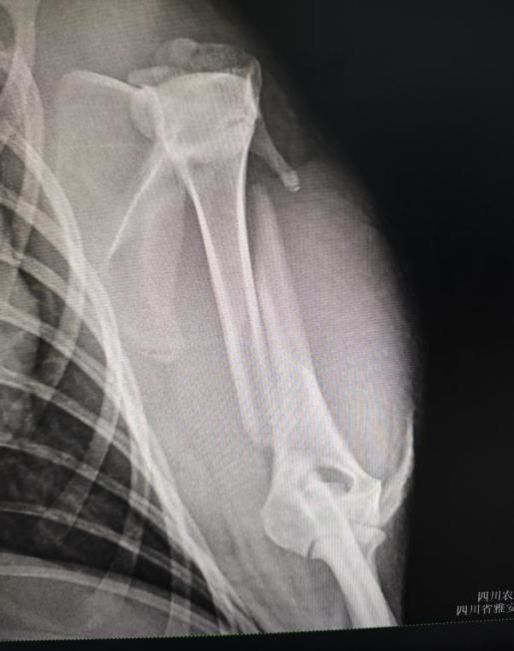

水豚,一种原本生活在南美洲亚马逊河流域的珍稀哺乳动物,因其独特的生理结构和萌宠的外貌而备受关注。本次手术的主角是一只因肱骨骨折而生命垂危的水豚。经过专家团队的精心评估和准备,手术于本周初顺利进行。

手术前左前肢腹背位X光